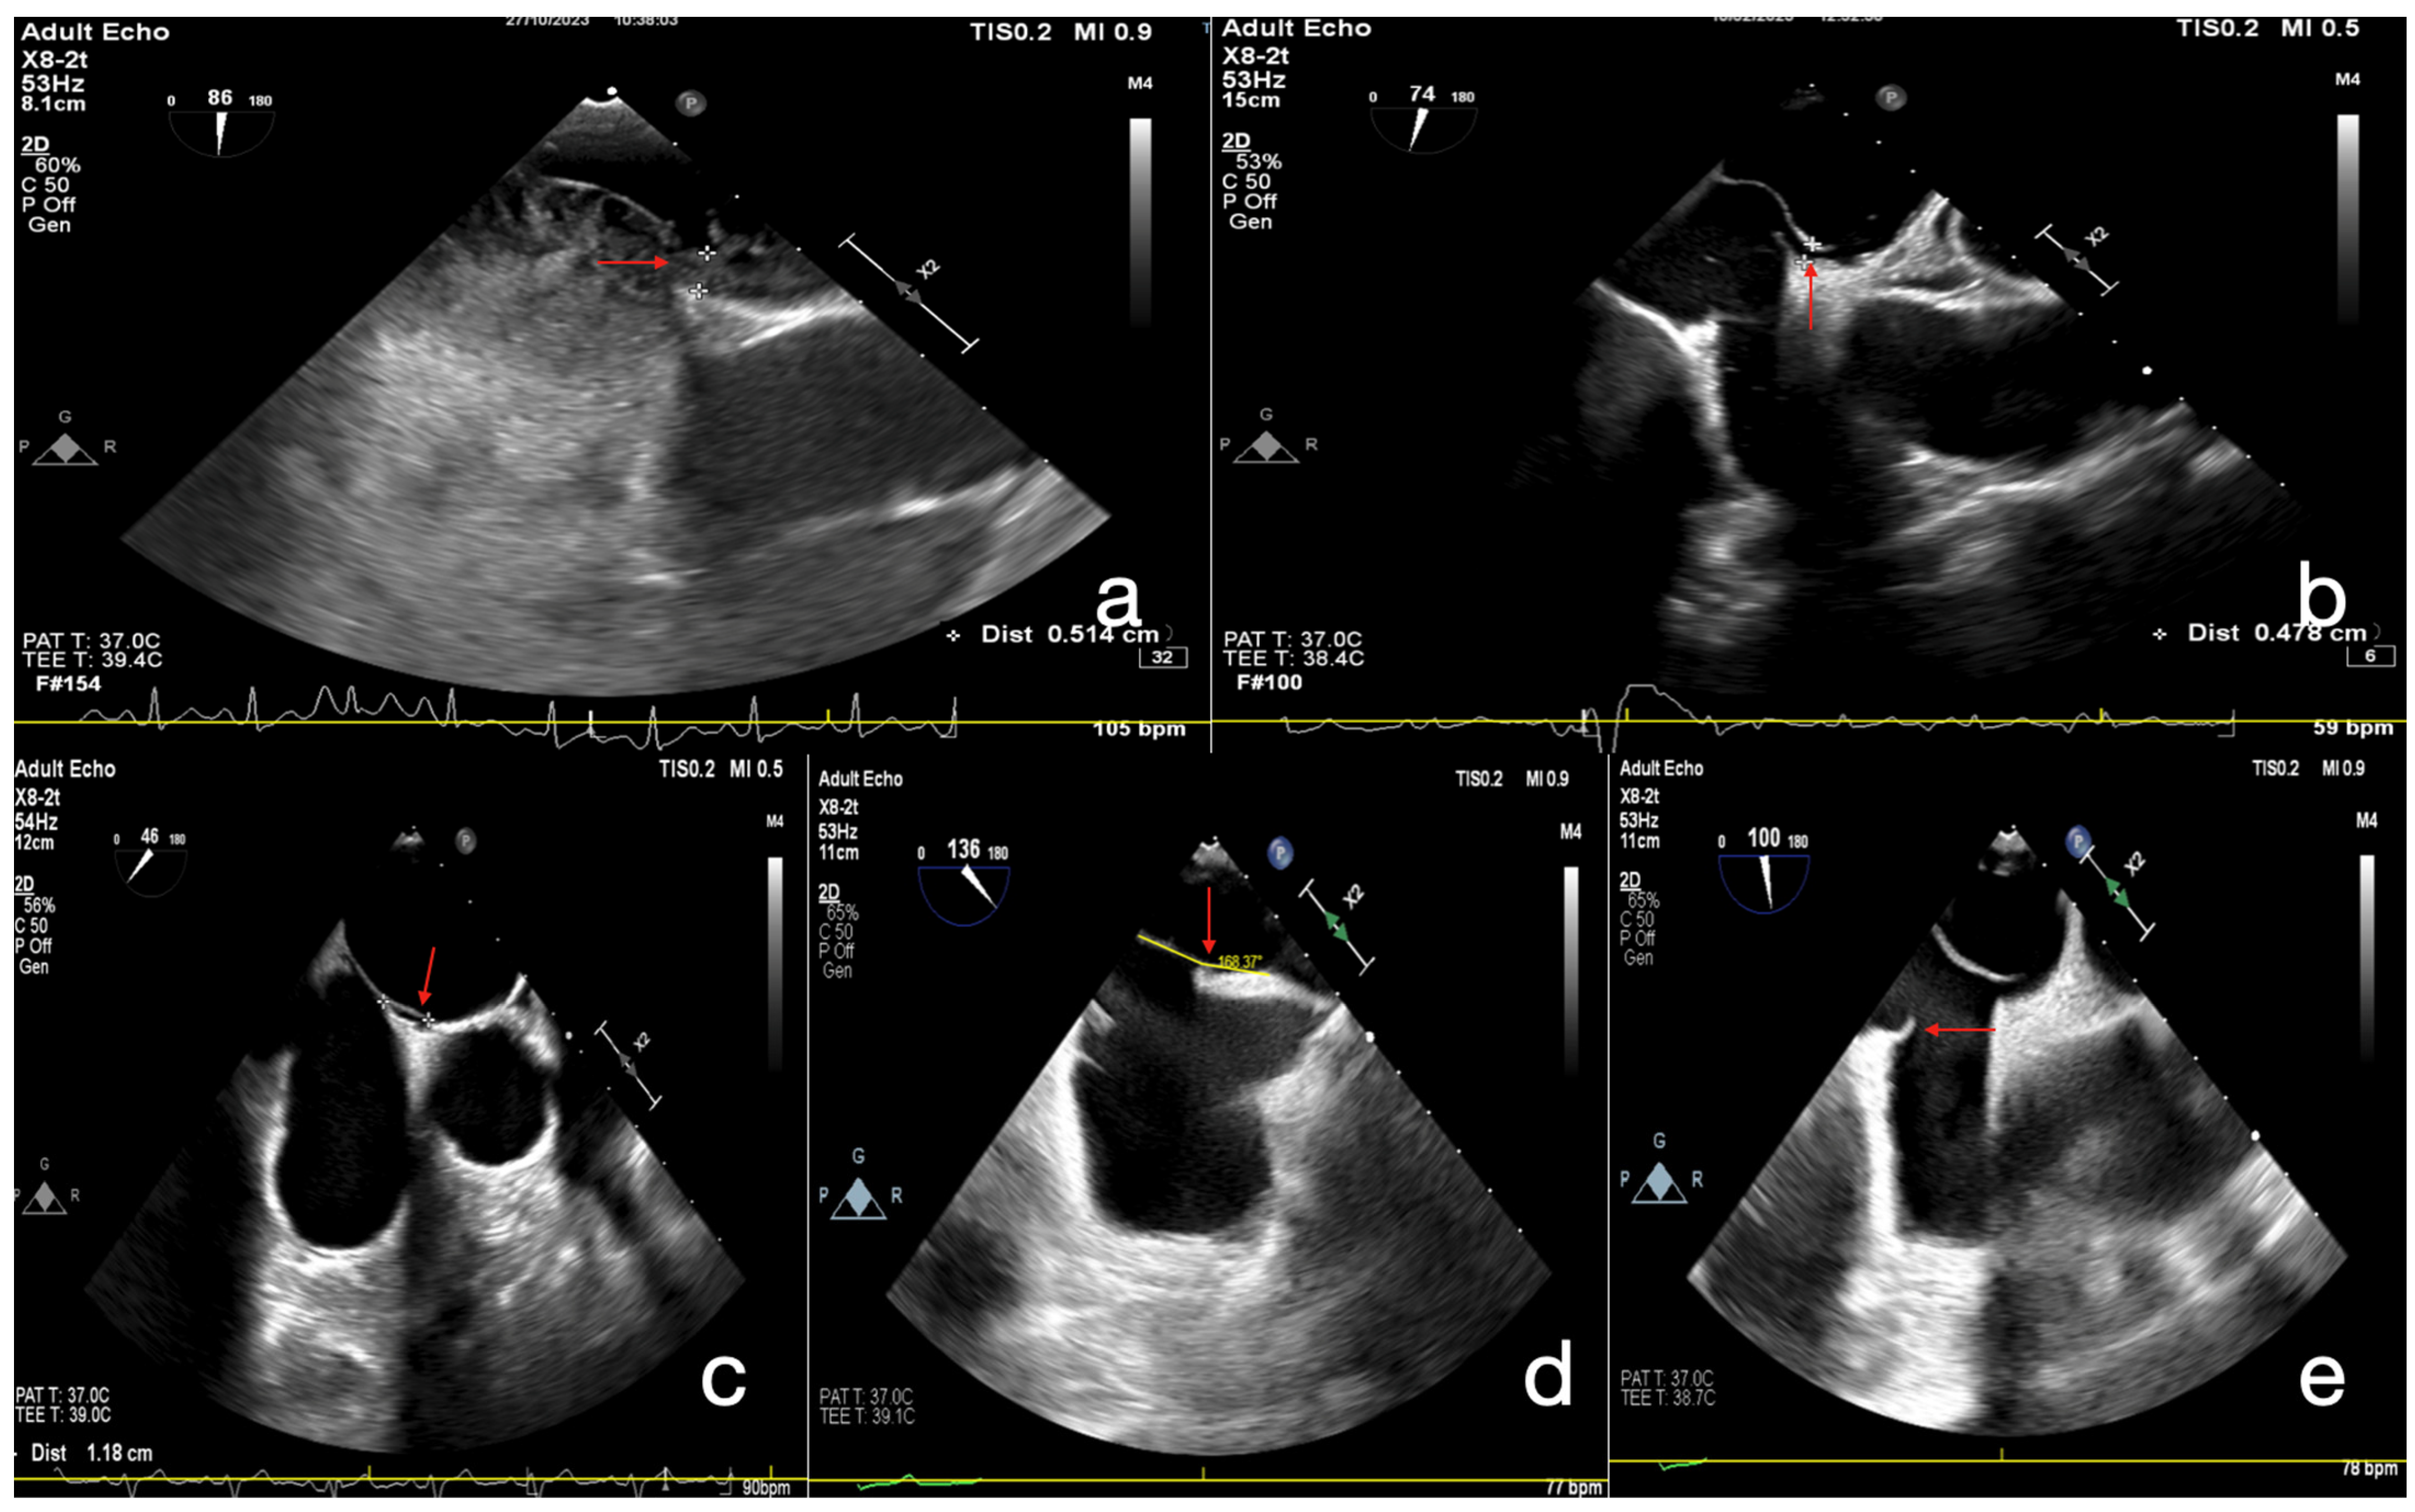

2.3. Echocardiographic Assessment